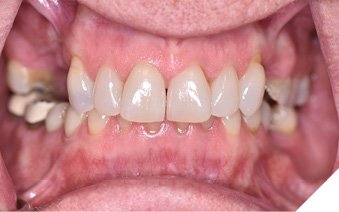

Articulated diagnostic casts showed very limited to no overjet and 90% of overbite. The wear pattern on the palatal aspect of her maxillary teeth appeared to be secondary to her tight occlusion since mandibular anterior teeth were in close contact with these surfaces with no “room” for protrusive movements. The diagnosis for this patient was: partial edentulism, failing existing restorations and attrition and abfraction secondary to parafunction. We discussed different options, including orthodontics in order to increase her overjet so we could have prosthetic space to restore her worn down teeth. We also discussed tooth replacement options. After a second consultation appointment which she attended with her husband, she decided that she did not want to replace her teeth with removable prosthetics. She also declined referral to an orthodontist. After discussion of multiple options of treatment to address all her chief complaints, her treatment consisted of a full mouth reconstruction with full coverage restorations in Zirconia for teeth 11-13,17,22-23,25-27,32-42, 44-47 and partial coverage restorations with lithium disilicate restoration for teeth 33,34 and 43. Replacement of teeth was achieved with a fixed partial denture to replace tooth 36 and a 3-unit implant supported bridge to replace teeth 24-26. In terms of occlusion, we created a more favorable occlusion with a proper anterior guidance, canine disclusion with more freedom for protrusive movements, which hopefully would decrease the parafunction, and alleviate some of her muscle pain. Before completing the case, the patient spent several weeks with provisional restorations which reflected the increase in vertical dimension of occlusion and the new occlusal scheme. During this trial phase, we assessed comfort, esthetics, function, decrease in pain and speech (Figs. 12-17).

Fig. 12

Fig. 13

Fig. 14

Fig. 15

Fig. 16

Fig. 17

During a 6 month follow up visit, the patient presented with reduced pain in her masticatory muscles and no sensitivity on her teeth. She was also pleased that her chewing function had improved and she loved her brighter smile. She used her night guard every night. She is in a 6-month recall protocol to ensure all restorations are in proper condition and that her occlusion continues to be ideal. We also monitor the health of the soft tissues and peri-implant health.